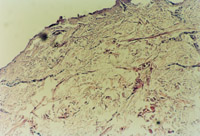

3-26 對大片的新生皮膚組織進(jìn)行組織學(xué)檢查,證實為生理性皮膚全層再生修復(fù)(傷后第49天)

3-27 已融合成新皮膚的區(qū)域,可見皮下組織大血管的解剖生理結(jié)構(gòu)形成